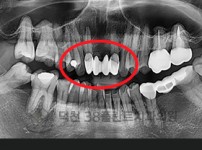

치료전후